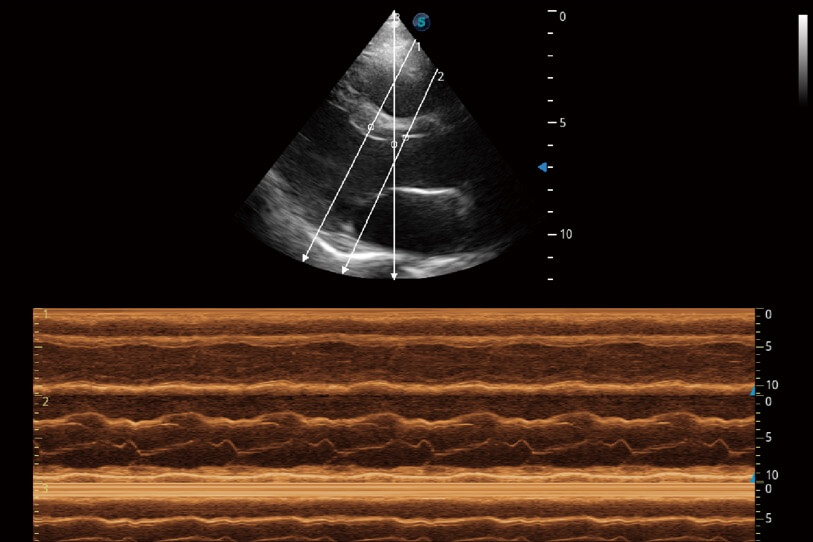

通過360度任意調(diào)節(jié)3條M型取樣線,在同一心動(dòng)周期上觀察心臟不同位置的運(yùn)動(dòng)曲線,得到準(zhǔn)確的心功能測量數(shù)據(jù),有效評估心肌運(yùn)動(dòng)及左心室功能。